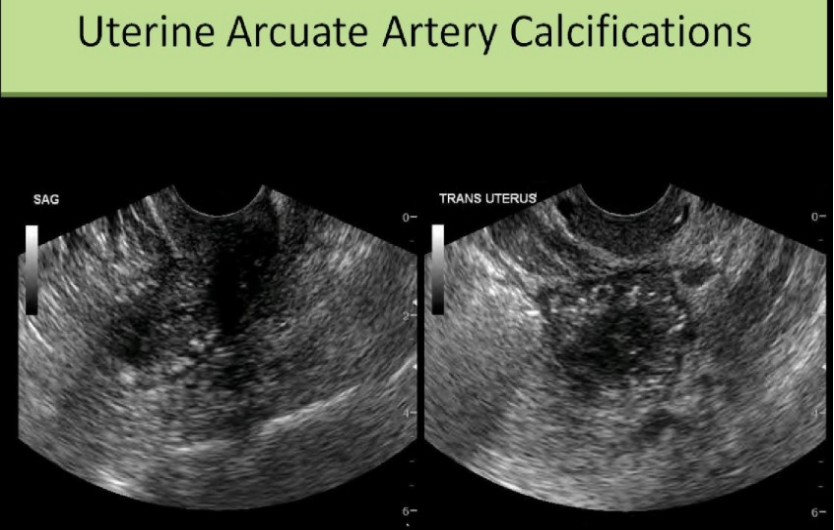

a 60 yo has hx of intermittent pelvic pain. the exam is normal except for the multiple small echogenic foci in the myometrium. which is the most common cause

.

a) systemic HTN

b) acute PID

c) diabetes

d) stein-levanthal syndrome